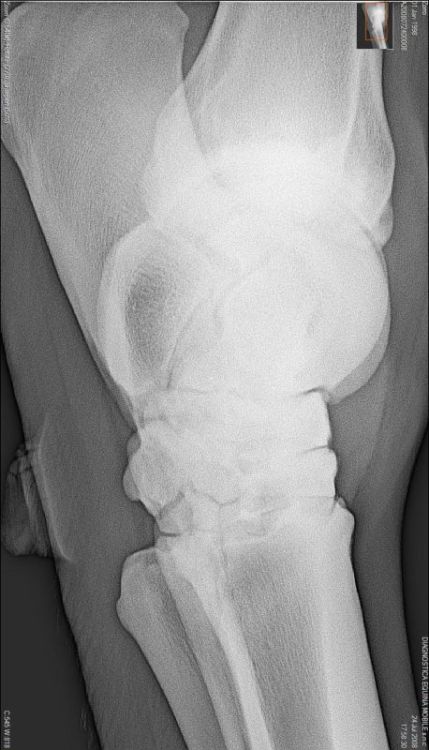

Briefly the radiographs show wear and tear changes common in many older working horses: osteophytes (bone spurs), calcification on the anterior of the pastern, partial calcification of the collateral cartilages. I do not see any definitive congenital defects. The talus of the hock has some odd irregularity but I don't review many digital radiographs and this could be a range of normal for it.

It depends on what you mean by arthritis. Do I see any lesions that correlate with painful arthritis 100% of the time? The answer is no. But yes there are osteophytes visible in both the tibiotarsal and proximal intertarsal joints (the upper two). The talus within the tibiotarsal joint also show evidence of bony resorption and production. These are markers for the presences of osteoarthritis.